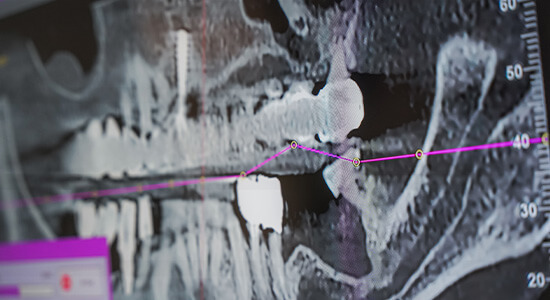

Badaniem jednoznacznie określającym poziom kości we wszystkich płaszczyznach jest tomografia komputerowa (CBCT). Na podstawie zdjęcia i specjalnie stworzonego oprogramowania, możemy dokładnie zmierzyć kość co do dziesiętnych części milimetra.